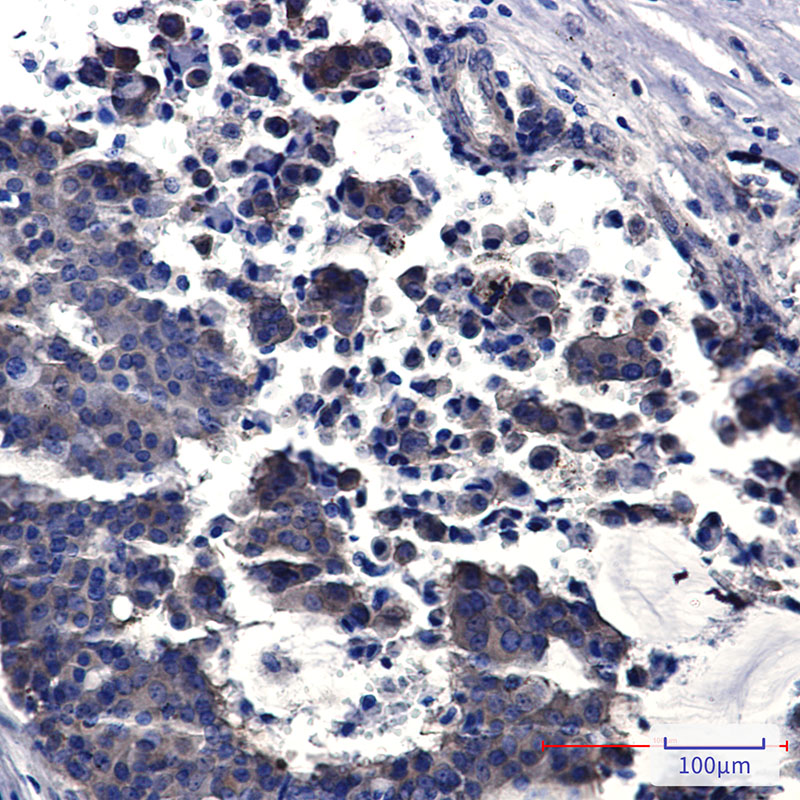

分类: 科研抗体货号: P22516别名: PRDX1; PAGA; PAGB; TDPX2; Peroxiredoxin-1; Natural killer cell-enhancing factor A; NKEF-A; Proliferation-associated gene protein; PAG; Thioredoxin peroxidase 2; Thioredoxin-dependent peroxide reductase 2应用: WB,IP,IF反应种属: Human,Mouse